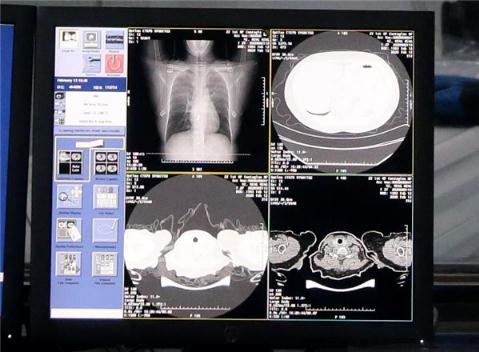

記者從阿里達摩院獲知,達摩院最新 AI 算法診斷技術(shù)可在 20 秒內對新冠疑似案例 CT 影像做出判讀,分析結果準確率達到 96%。該算法輔助診斷技術(shù)將在 2 月 16 日起在河南鄭州小湯山啟用。

根據國家衛健委公布的診療方案第五版,臨床診斷無(wú)需依賴(lài)核酸檢測結果,CT 影像臨床診斷結果可作為新冠肺炎病例判斷的標準。新冠肺炎患者的 CT 的影像特征表現為單肺或雙肺多發(fā)、斑片狀或節段性磨玻璃密度影等細微變化。

據阿里達摩院介紹,達摩院醫療 AI 團隊基于當前最新的診療方案、鐘南山等多個(gè)權威團隊發(fā)表的關(guān)于新冠肺炎患者臨床特征的論文,與多家機構合作,基于 5000 多個(gè)病例的 CT 影像樣本數據,學(xué)習訓練樣本的病灶紋理,研發(fā)全新的 AI 算法模型。通過(guò) NLP 自然語(yǔ)言處理回顧性數據、使用 CNN 卷積神經(jīng)網(wǎng)絡(luò )訓練 CT 影像的識別網(wǎng)絡(luò ),AI 可以快速鑒別新冠肺炎影像與普通病毒性肺炎影像的區別,最終識別準確率高達 96%。AI 每識別一個(gè)病例平均只需要不到 20 秒,大大提高診斷效率,減輕醫生壓力。

達摩院透露,除了率先落地的河南鄭州小湯山醫院,AI 算法輔助診斷還將在湖北、廣東、安徽等地近 100 家醫院落地。